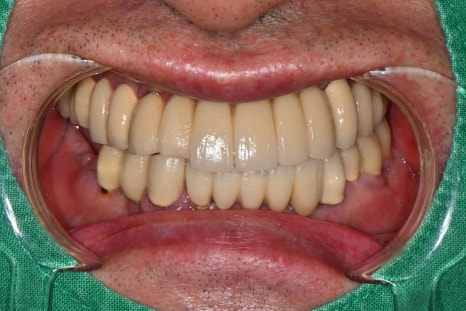

Left photo: Front view of the completed prosthesis. Both esthetics and function were restored satisfactorily.

Right photo: From the side as well, the natural curve and bite were well maintained, allowing comfortable chewing.